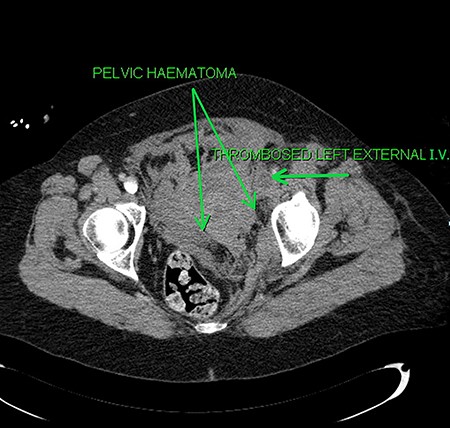

A 60-year-old Caucasian female was referred by her GP for a 2-day history of pain and swelling of the left leg. On examination, there was obvious limb swelling and a mass in the left iliac fossa. Soon after the presentation, the patient became hypotensive and arrested requiring cardiopulmonary resuscitation (CPR). The initial working diagnosis was PE secondary to DVT. Baseline investigations were normal but arterial blood gases showed compensated metabolic acidosis. After resuscitation, an urgent CT of abdomen, pelvis and chest was organized; this confirmed DVT of the left common iliac vein and also a large left adnexal mass with minimal ascites (Fig. 1). The patient, evidently in hypovolemic shock, was transferred for urgent exploratory laparotomy. She was found to have a large retroperitoneal haemorrhage with blood welling from the region of left iliac vessels. Proximal and distal control of iliac artery and vein was gained by tape and clamps allowing perioperative hypotension to improve. The vascular surgeon was called for help from the nearest tertiary centre. Upon further dissection, in the presence of the vascular surgeon, bleeding was noticed around the left common iliac vein, coming from the severed collaterals; these were eventually controlled with 6/0 prolene sutures. As the source of bleeding was not very clear, an opinion from vascular radiologist was sought. Review of the CT suggested that bleeding was likely to represent spontaneous rupture of venous collaterals due to DVT in the left iliac vein, secondary to MTS (Fig. 2). The patient was transferred to ITU with plans for relook surgery in next 48 hours once she had recovered from the acute insult. Unfortunately, the patient died the next day due to multi-organ failure and DIC secondary to massive transfusion.

Axial sections of the CT scan showing the thrombosed external iliac vein (I.V.) and the pelvic haematoma.